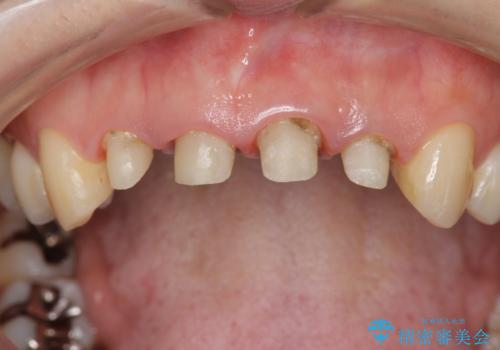

金属を用いたコア・クラウンが装着されており、全ての金属を除去したのちのメタルフリー治療を計画します。

ファイバーコア・セラミッククラウンは金属を用いない審美的な治療法です。

- 44万円(エコノミークラウン×4・ファイバーコア×4・仮歯×4)費用は治療当時の料金となります